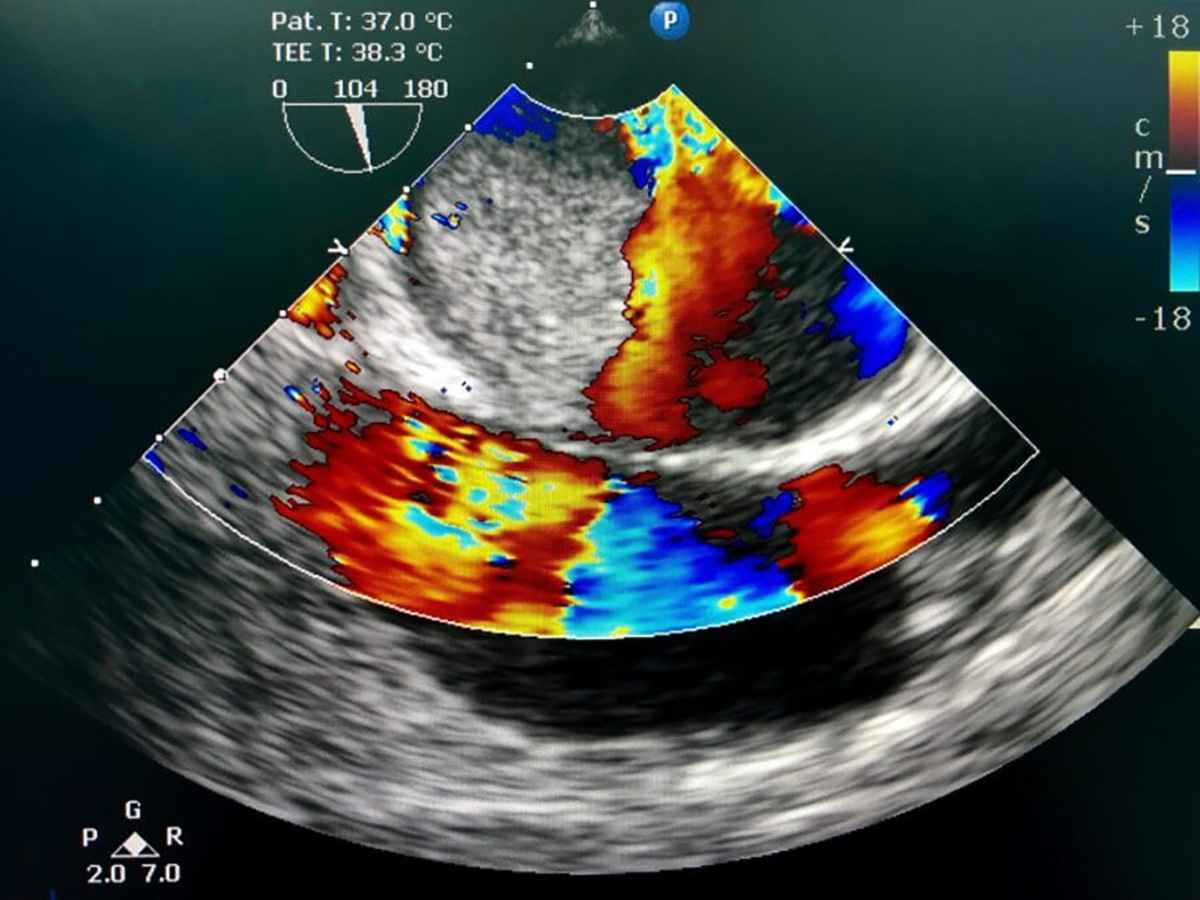

3. اکوکاردیوگرافی از طریق مری (TEE) این روش با قرار دادن مبدل در مری انجام می‌شود و تصاویر دقیق‌تری از ساختارهای داخلی قلب ارائه می‌دهد، به خصوص در بیماران با بیماری‌های پیچیده دریچه‌ای.

4. اکوکاردیوگرافی داپلر این روش برای ارزیابی جریان خون در داخل قلب و عروق استفاده می‌شود و به تشخیص ناهنجاری‌های جریان خون کمک می‌کند.

تصویر داپلر رنگی اکوکاردیوگرافی؛ ارزیابی جریان خون قلب و نشت دریچه‌ای